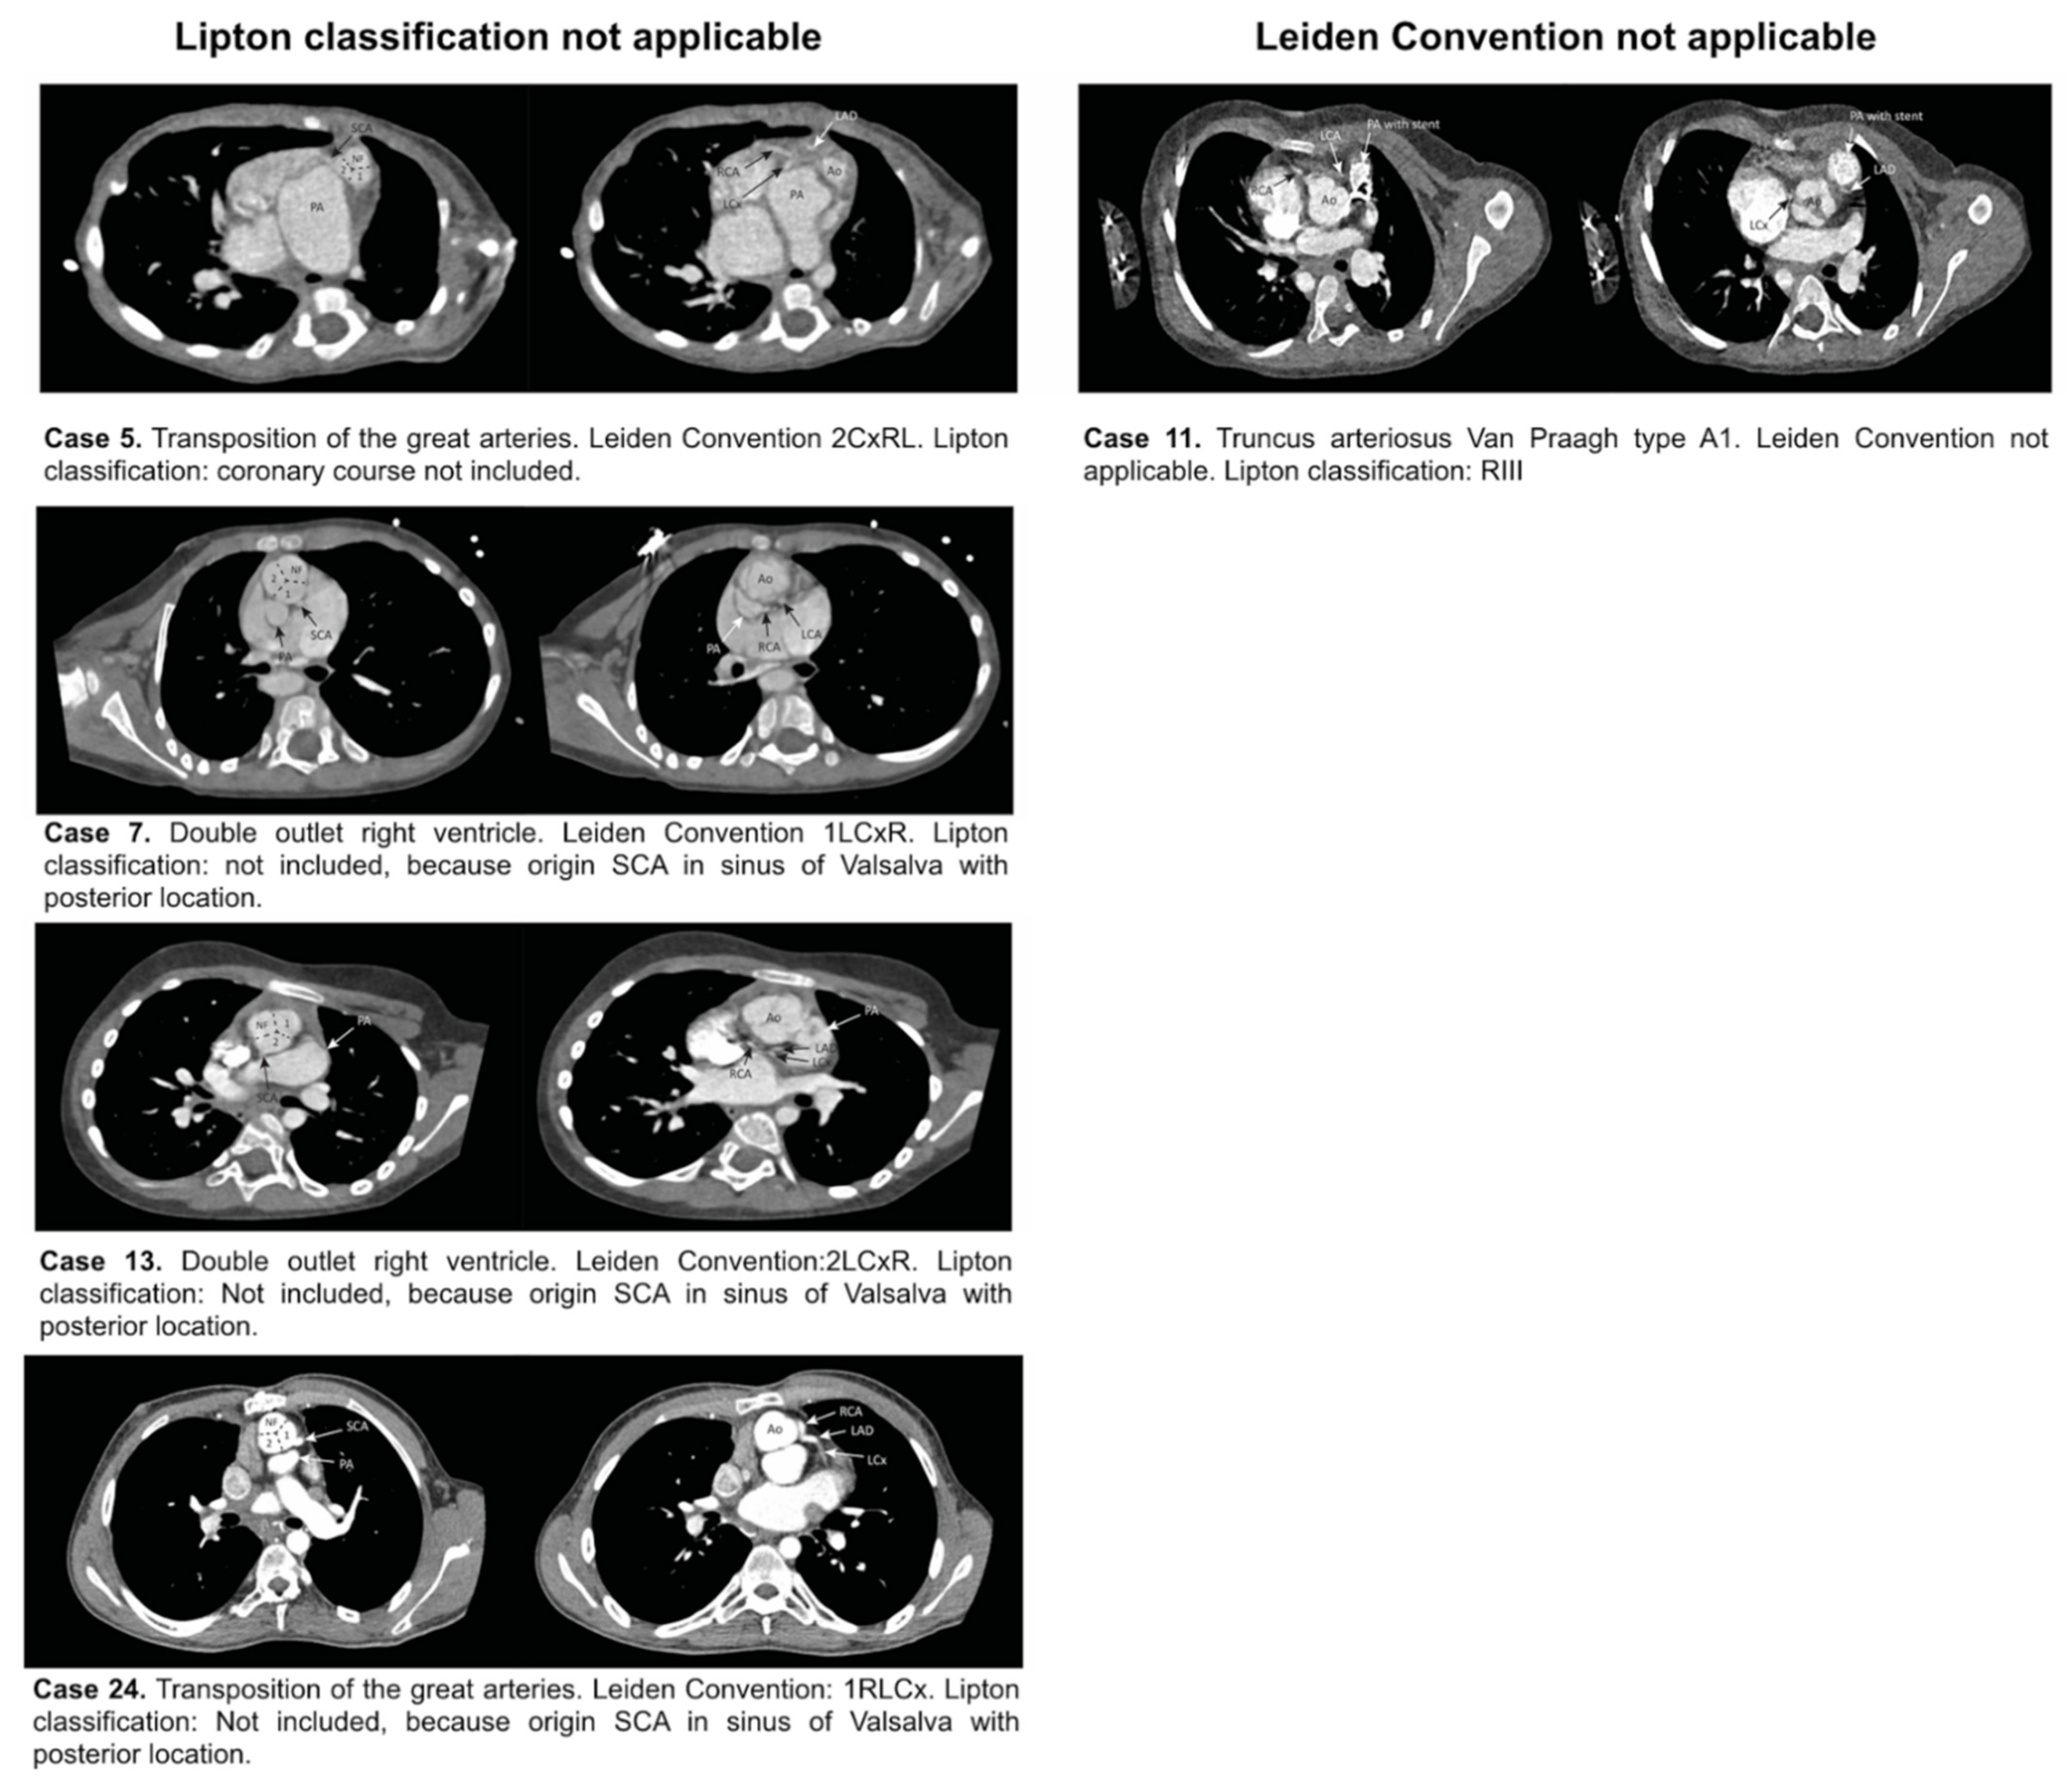

| Lipton classification applicable, Leiden Convention not applicable (Figure 5) | ||

| Lipton classification not applicable, Leiden Convention applicable (Figure 5) | ||

| 5 | Course not included | 2CxRL |

| 7 | Posterior sinus | 1LCxR |

| 13 | Posterior sinus | 2LCxR |

| 24 | Posterior sinus | 1RLCx |

| 5 | F | 8M | Transposition of the great arteries | Left anterior | 2CxRL | NI* | None |

| 7 | M | 3Y | Double-outlet right ventricle. Common atrioventricular canal type C of Rastelli. Right aortic arch | Left anterior | 1LCxR | NI* | None |

| 13 | F | 6Y | Double-outlet right ventricle | Right anterior | 2LCxR | NI* | None |

| 24 | M | 16Y | Transposition of the great arteries | Right anterior | 1RLCx | NI* | None |